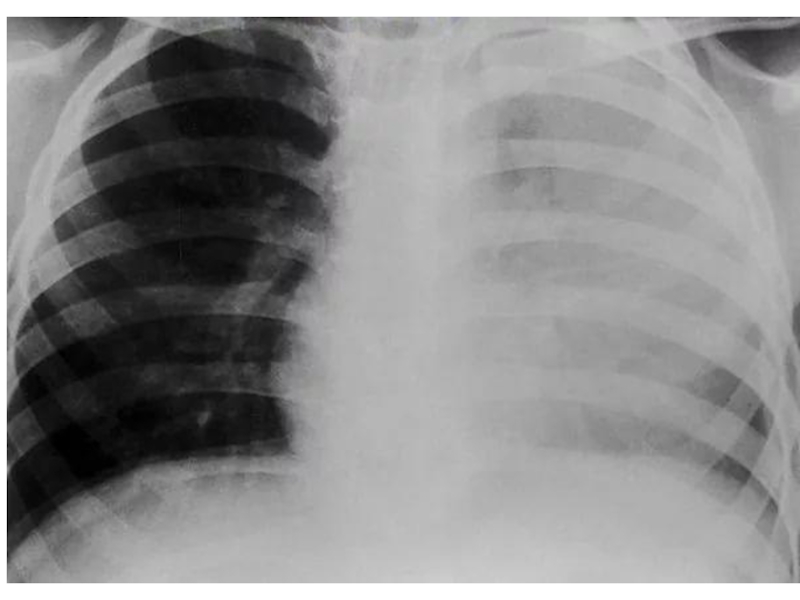

Слайд 61Правосторонний плеврит

Правосторонний плеврит